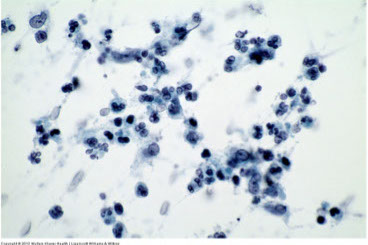

Chronic sialadenitis

Chronic sialadenitis

Firm, diffusely enlarged gland that mimics neoplasm (MC in submandibular gland), usually unilateral

- may be 2/2 duct obstruction cuased by stones, radiation, immunologic disorders, or infx

- FNA usually painful c scant cellular material (paucicellular c few acinic cells), can have reactive ductal cells, variable chronic inflam (lymphs), stromal fragments (fibrous tissue), proteinaceous debris

chronic sialadenitis

Chronic sialadenitis